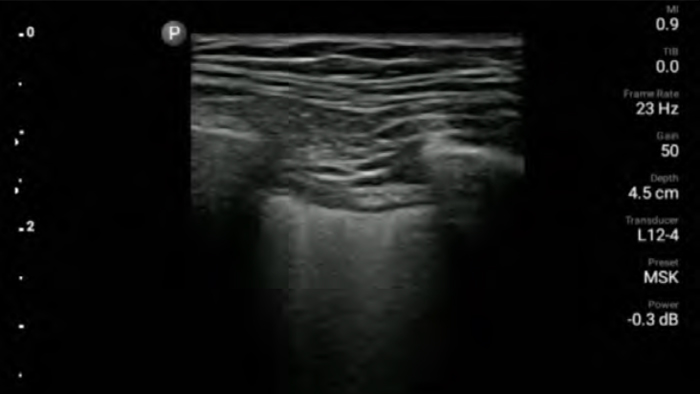

Lumify handheld ultrasound for anesthesiology helps you clearly visualize border definition with your needle placement, surrounding nerves, vessels and fascial planes.

From revealing the subtle details of an image to uncovering enriched tissue definition from multiple angles, Lumify can help you make real-time decisions with more confidence from assessment through recovery.